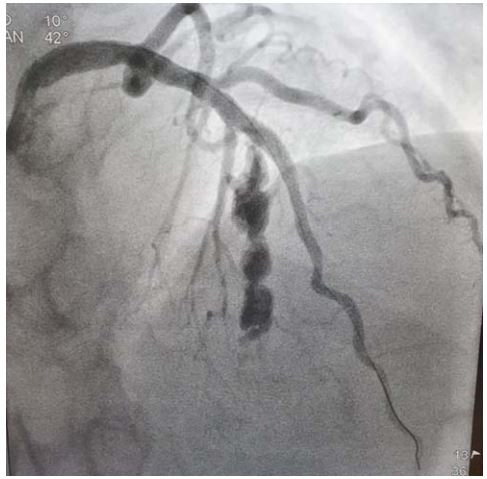

Mulher de 67 anos hipertensa e dislipidemia procurou atendimento médico com dor torácica de forte intensidade com duração há 2 horas. ECG de admissão revelou supra ST na parede anterior. Foi submetida a angioplastia primária. O controle após a angioplastia é representado a seguir:

Enunciado 2129481-1

Qual é diagnóstico mais provável: